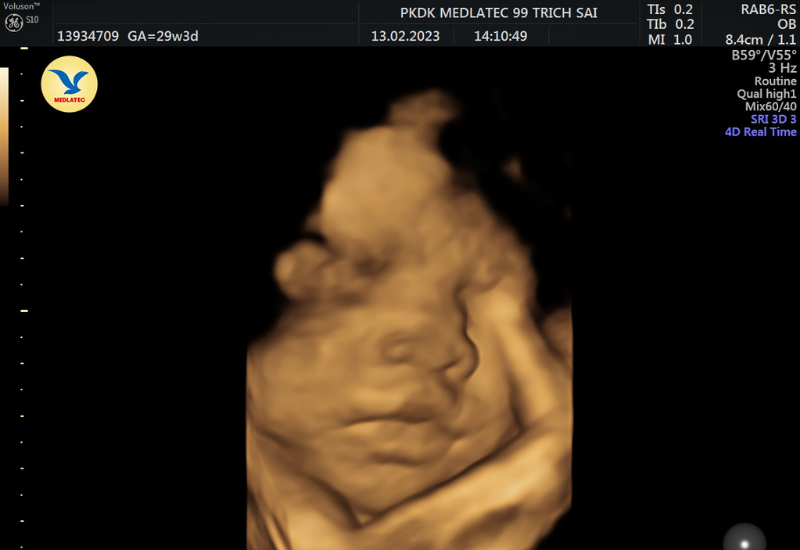

- Siêu âm 3D: Công nghệ siêu âm 3D sử dụng hình ảnh tĩnh ba chiều, giúp tái hiện rõ khuôn mặt, tay, chân và các đường nét cơ thể của bé một cách sống động hơn so với siêu âm 2D.

Siêu âm 3D sử dụng hình ảnh tĩnh ba chiều, giúp tái hiện khuôn mặt thai nhi rõ nét và chân thực

- Siêu âm 4D: Siêu âm 4D là bước tiến vượt bậc so với công nghệ 3D. Ngoài việc tái hiện hình ảnh ba chiều, kỹ thuật này còn cho phép ghi lại chuyển động của thai nhi theo thời gian thực. Mẹ bầu có thể thấy con đang cười, ngáp hay đưa tay lên mặt, mang đến trải nghiệm đầy xúc động và sống động như đang nhìn trực tiếp vào bé.

- Từ tuần 26 đến 32: Đây được xem là thời kỳ vàng để quan sát khuôn mặt thai nhi. Hình ảnh siêu âm lúc này cho thấy rõ các biểu cảm sinh động, làn da và từng chi tiết nhỏ trên khuôn mặt bé.